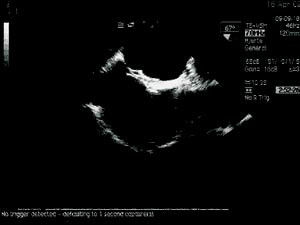

Transøsofageal ekkokardiografi ble utført med pasienten i venstre sideleie og lett sedert. Atrieseptum sees vanligvis best fra en midtøsofageal firekammer- eller langakseposisjon (22). Saltvannskontrast bestående av 8 ml saltvann med 2 ml oppslemmet luft ble satt i en vene på høyre arm. Man registrerte så eventuell overgang av mikrobobler fra høyre til venstre forkammer (23). Kontrasttesten ble utført uten og med Valsalvas manøver.

Via en 9 french (F) hylse i høyre v. femoralis, føres et kateter gjennom åpentstående foramen ovale til venstre forkammer og videre til høyre øvre lungevene. Fra denne posisjonen gjøres angiografi for å kartlegge atrienes anatomi. Deretter plasseres et ballongkateter i foramen ovale, og en måler såkalt strukket diameter, som senere brukes til å bestemme paraplystørrelse (fig 2). Ballongkateter og 9 F hylse fjernes og en lang hylse på 11 F føres til venstre forkammer. Pasienten gis heparin 7 500 IE intravenøst. En CardioSEAL paraply (Nitinol Medical Technologies, Boston, USA) (fig 3) lades i et spesielt innføringskateter, slik at de to delene folder seg sammen hver sin vei (fig 4). Paraplyen føres til venstre forkammer hvor den distale delen av paraplyen frigjøres ved at den skyves ut av innføringskateteret. Hele enheten trekkes så mot septum før man løser ut den proksimale del av paraplyen i høyre forkammer. Hele prosedyren foregår under veiledning av transøsofageal ekkokardiografi og gjennomlysning. Ved riktig posisjon står paraplyen sentralt i åpentstående foramen ovale med fire bein hvilende på hver side av atrieseptum og kan frigjøres (fig 5, 6).